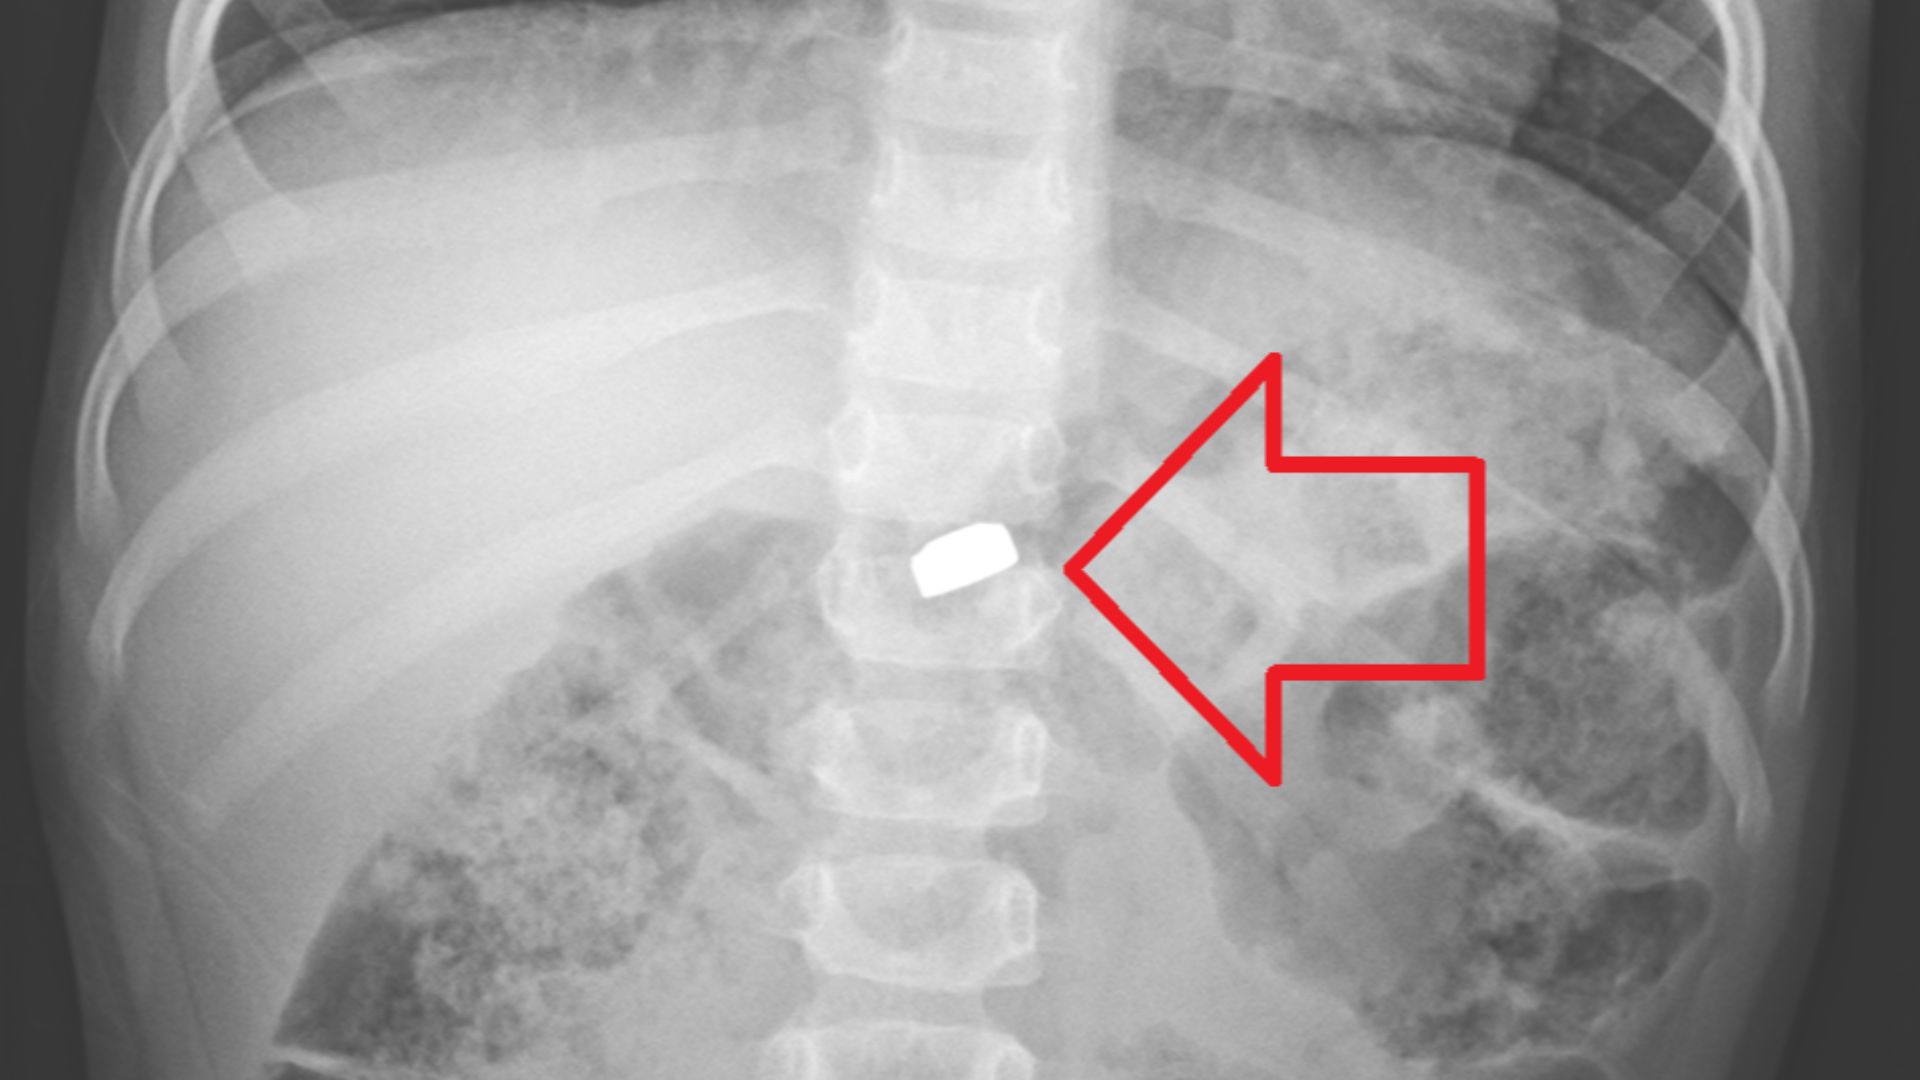

Based on this image's title: “8 household products that are dangerous for kids”